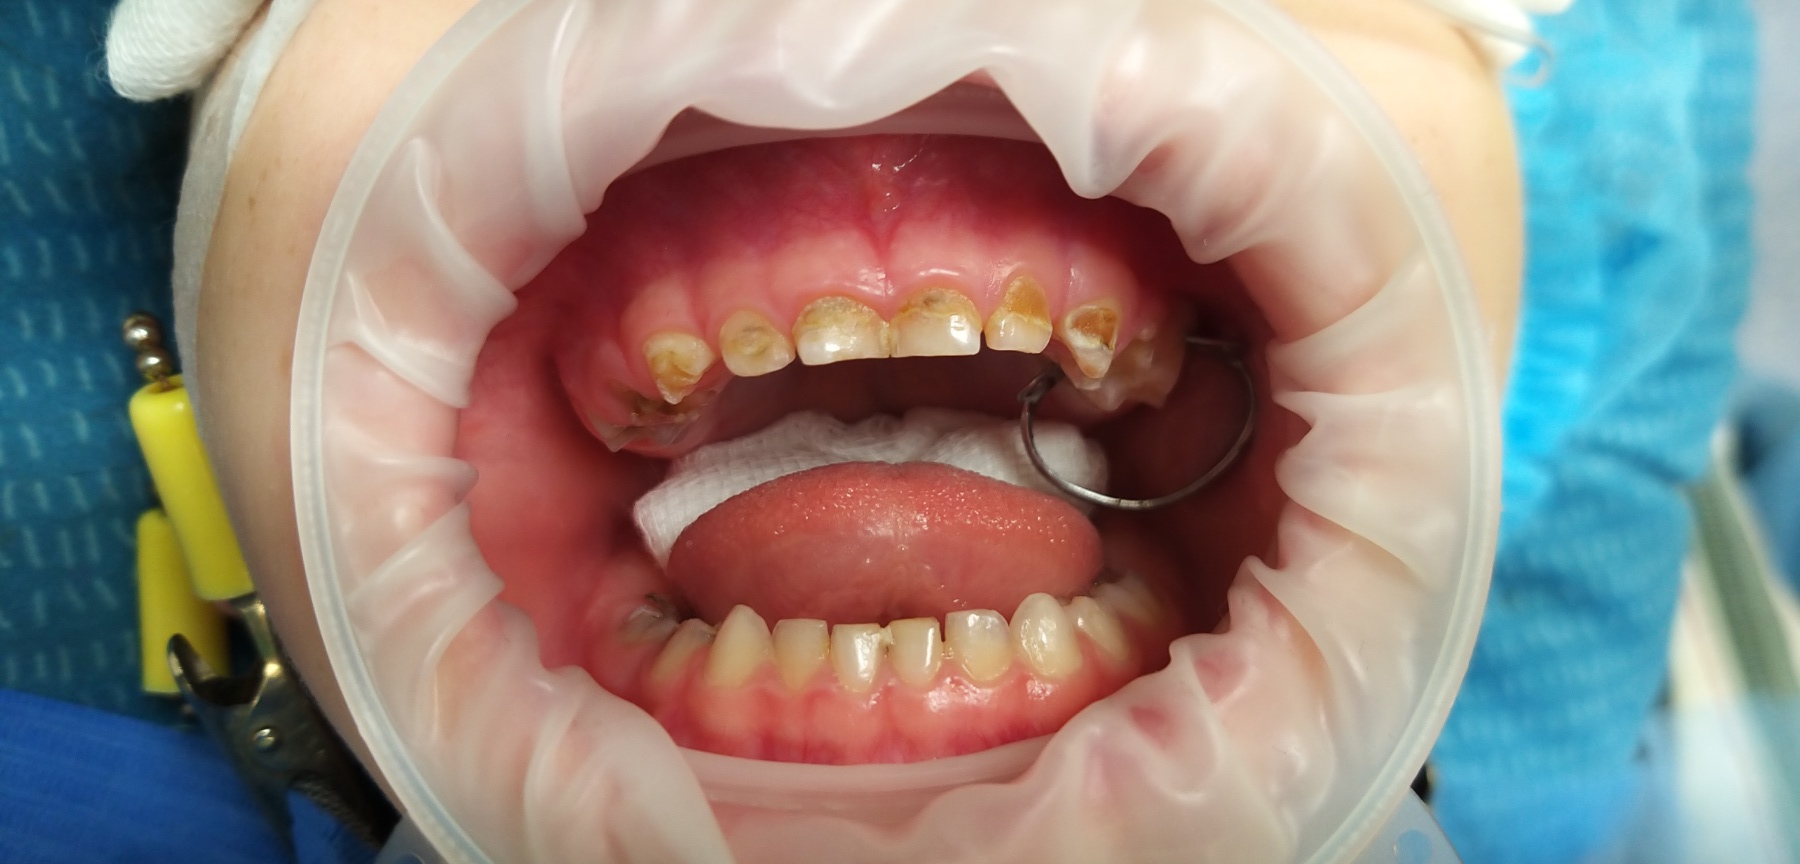

Лікар стоматолог - терапевт